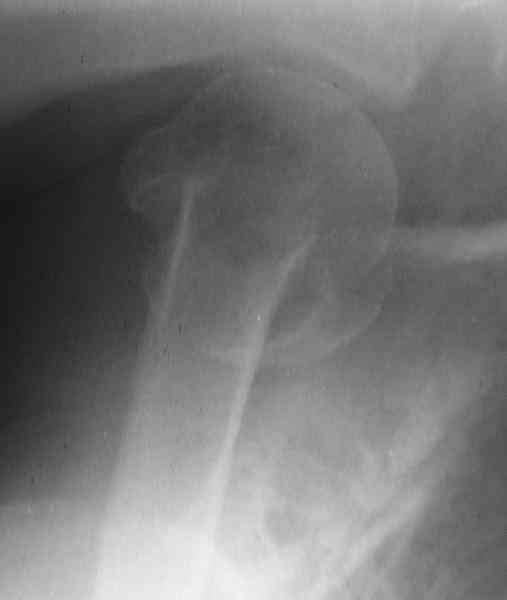

CT scans would be useful to evaluate the head.

Fragments now look severely displaced.